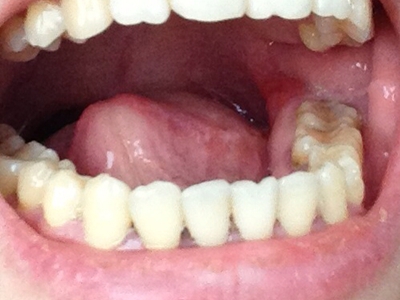

智齿冠周炎智齿周围牙龈红肿图

智齿冠周炎表现为牙列尽头智齿阻生,一部分智齿未萌出,周围的牙龈红肿,空隙变大,并有食物残渣潴留,患者自觉病变位置疼痛,并伴有张口受限及咀嚼困难。